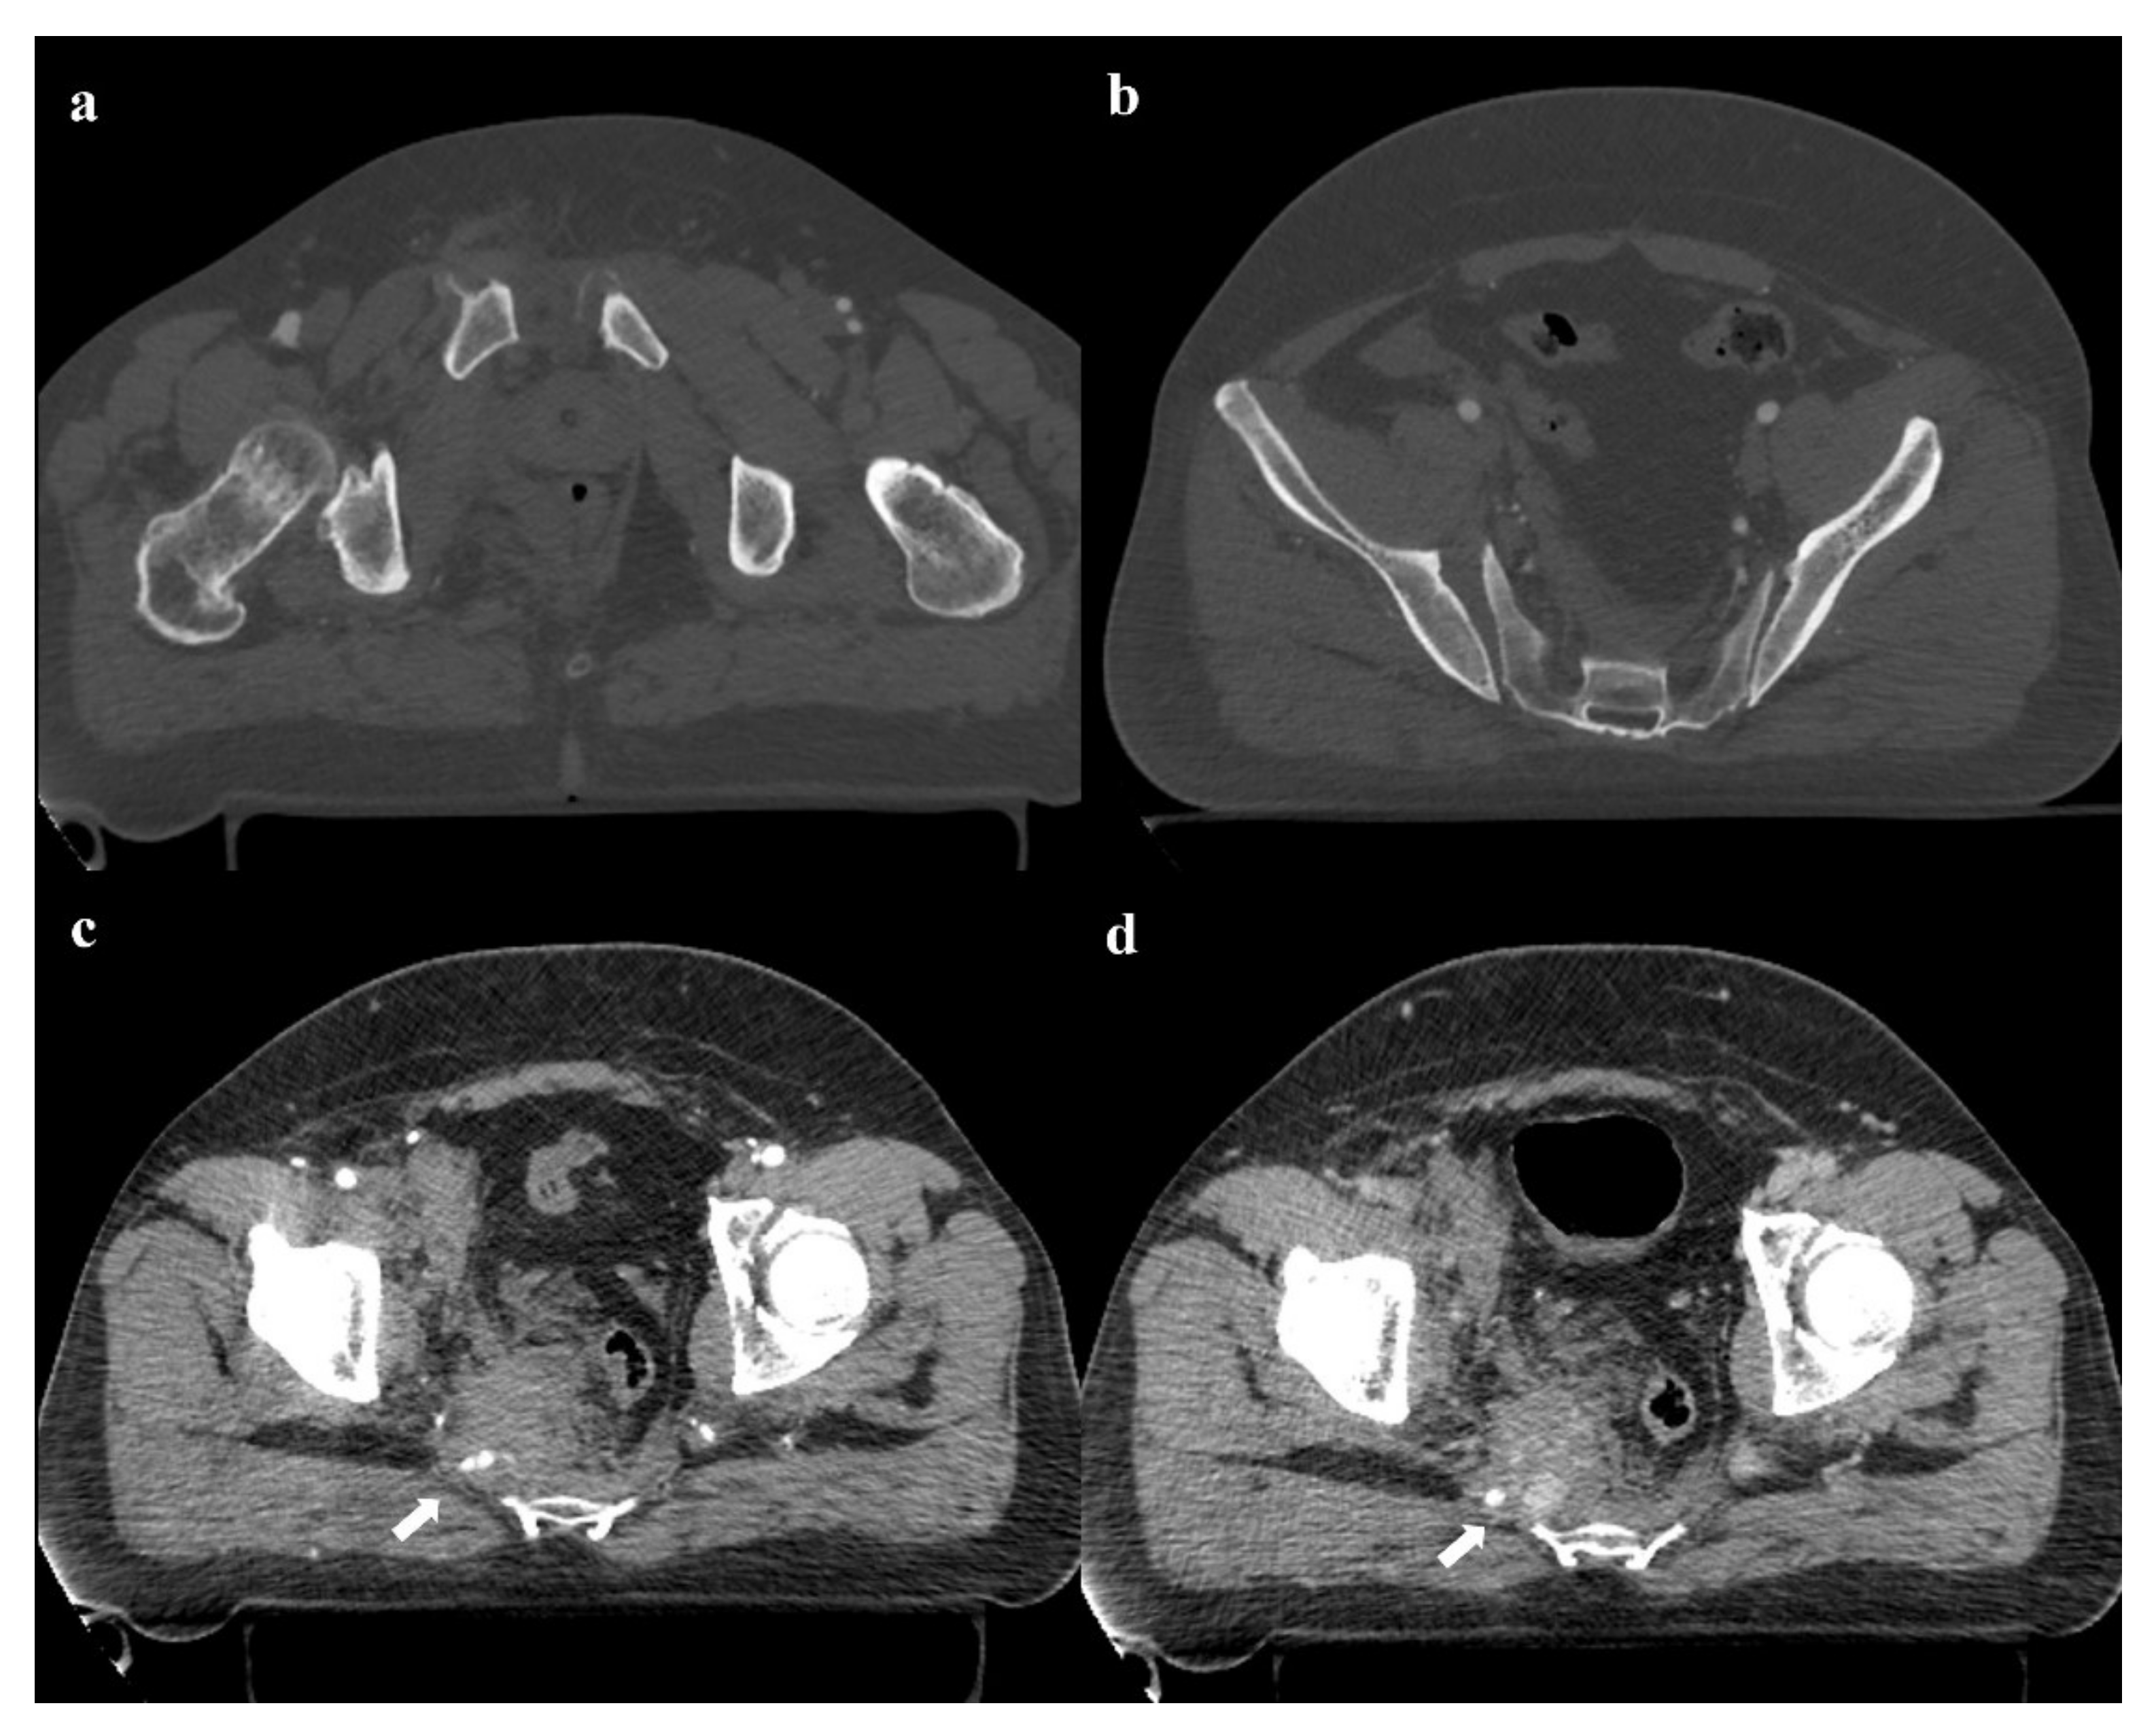

• Grade 3: the lateral compression force is associated with a contralateral anteroposterior compression force, with an external rotation of the contralateral hemipelvis (“windswept pelvis”). Grade 1 or grade 2 lateral compression injuries are associated with a contralateral sacroiliac joint diastasis (Figure 3). Lateral compression grade 3 injuries have a multidirectional instability and require a stable internal fixation [3]. In these lesions, an adjunctive temporary external fixation is useful [3].

Figure 3. Lateral compression fracture, type 3. Axial CT images show the fracture of the iliac and sacral wings on the left side (a), anterior widening of the right sacroiliac joint (b), and fracture of bilateral pubic branches (c,d).